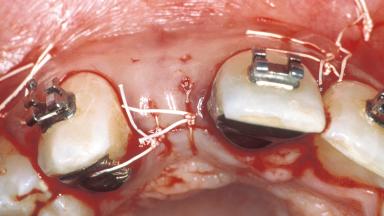

Mauricio Araujo and Flauvia Matarazzo present this straightforward clinical case, demonstrating the potential effect of implant placement depth on the resolution of peri-implant treatment. A 42-year-old systemically healthy female patient, a non-smoker with no history of periodontitis, was treated at the Dental Clinic at the State University of Maringá, Brazil between 2008 and 2009, when she received five implants restored with single crowns at sites 14, 26, 27, 36, and 46. After delivery of the implant-supported prosthetic restorations, the patient was enrolled in the supportive peri-implant therapy (SPiT) maintenance program at the same university.